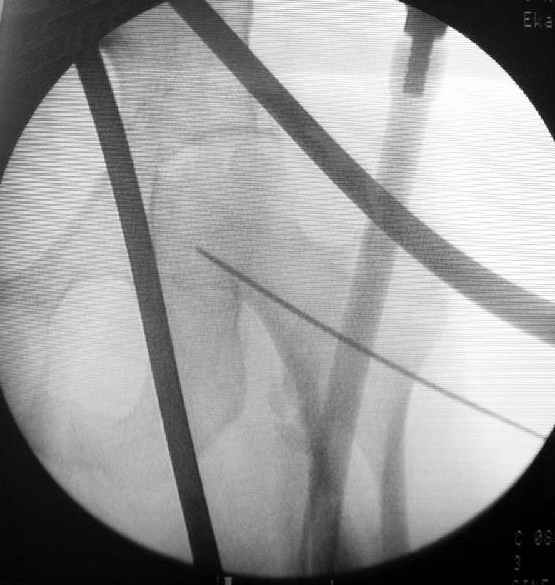

Как раз недавно у меня был примерный случай: больному 36 лет, поступил ночью, травма в результате мотоциклетной аварии, кроме чрезвертельного и спирального перелома левого бедра имеется переломы костей предплечья с этой же стороны. Скелетное вытяжение, а на следующий день больной про оперирован на ортопедическом столе с дистракцией. Чтобы не расколоть чрезвертельный перелом провели временную спицу ближе к переднему кортексу, из малого разреза костодержатель для репозиции, а фиксацию провели антиградным штифтом. Этапы операции на снимках.

Да, сейчас это и у нас самый напрашивающийся выбор. Сделали гвоздем ChM, картинки в приложении.